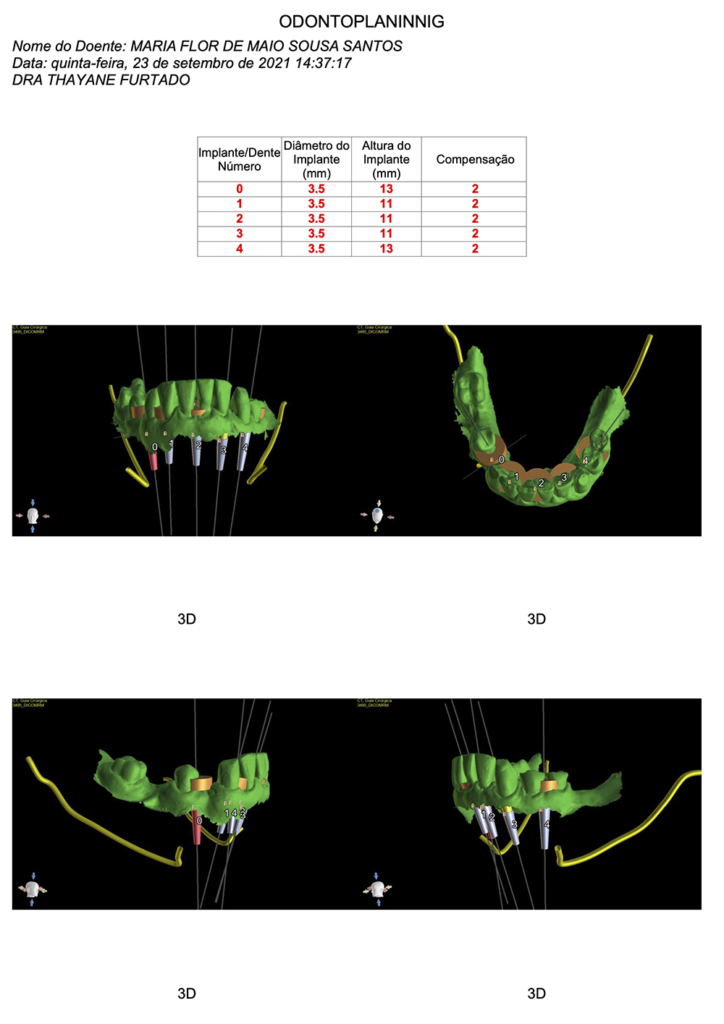

Através do escaneamento intraoral, foi realizado o planejamento das cirurgias guiadas (ODONTOPLANNING-BRASIL).

Impressão dos guias cirúrgicos superior e inferior.

Guia cirúrgico superior posicionado em boca antes das extrações dentárias.

Instalação dos implantes com o guia cirúrgico em posição.

Momento logo após a confecção dos implantes guiados superiores.